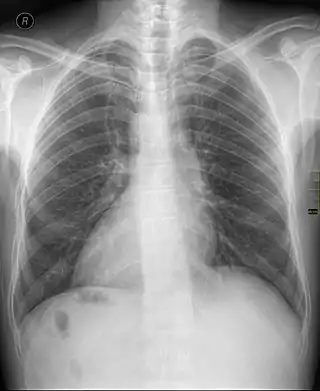

Dextrocardia (from Latin dextro, meaning "right hand side," and Greek kardia, meaning "heart") is a rare congenital condition in which the apex of the heart is located on the right side of the body, rather than the more typical placement towards the left.[1][2]

There are two main types of dextrocardia: dextrocardia of embryonic arrest (also known as isolated dextrocardia) and dextrocardia situs inversus. Dextrocardia situs inversus is further divided.

In this form of dextrocardia, the heart is simply placed further right in the thorax than is normal. It is commonly associated with severe defects of the heart and related abnormalities including pulmonary hypoplasia.[3]

Dextrocardia refers to a heart positioned in the right side of the chest. Situs solitus describes viscera that are in the normal position, with the stomach on the left side.[4]